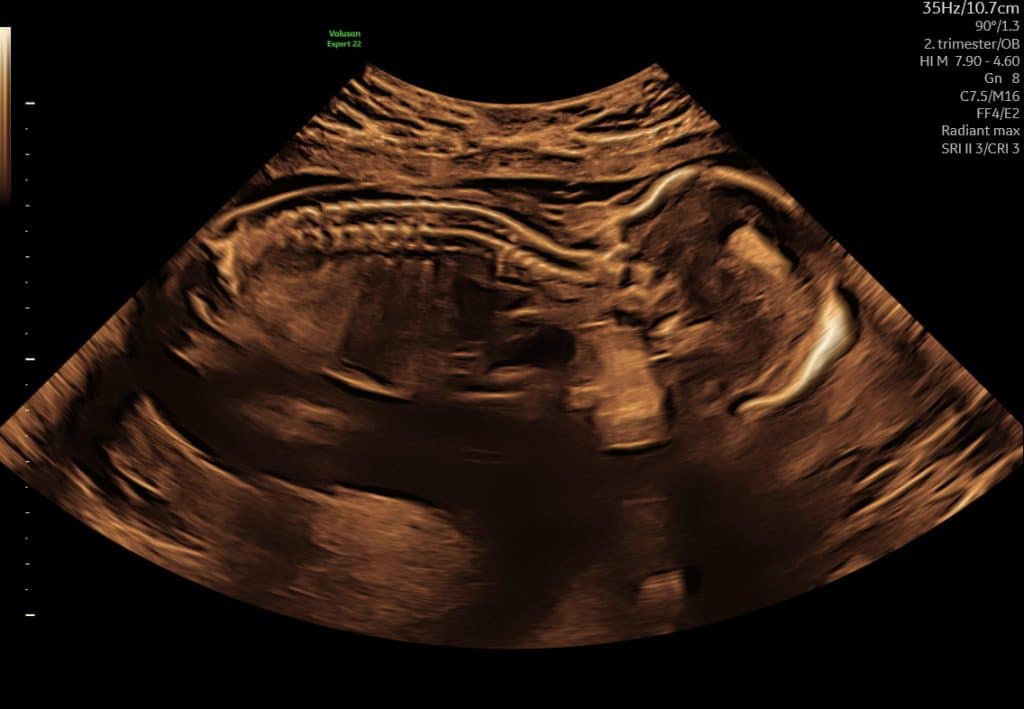

Ultralyd i uge 18–21

I denne periode udføres den store gennemgang af barnets anatomi i det offentlige. Ved ultralyd kan man typisk se:

- organer og kropsdele mere detaljeret

- rygrad, mave, blære og ekstremiteter

- barnets generelle trivsel

Fosteret fylder nu mere på skærmen, og det er ofte muligt at få meget klare billeder.

Ultralyd uge 18 ansigt i profil

Ultralyd i uge 18 som viser barnets rygsøjle set i længdesnit

Ultralyd i sen graviditet. Det er normalt, at man kun ser dele af barnet ad gangen.